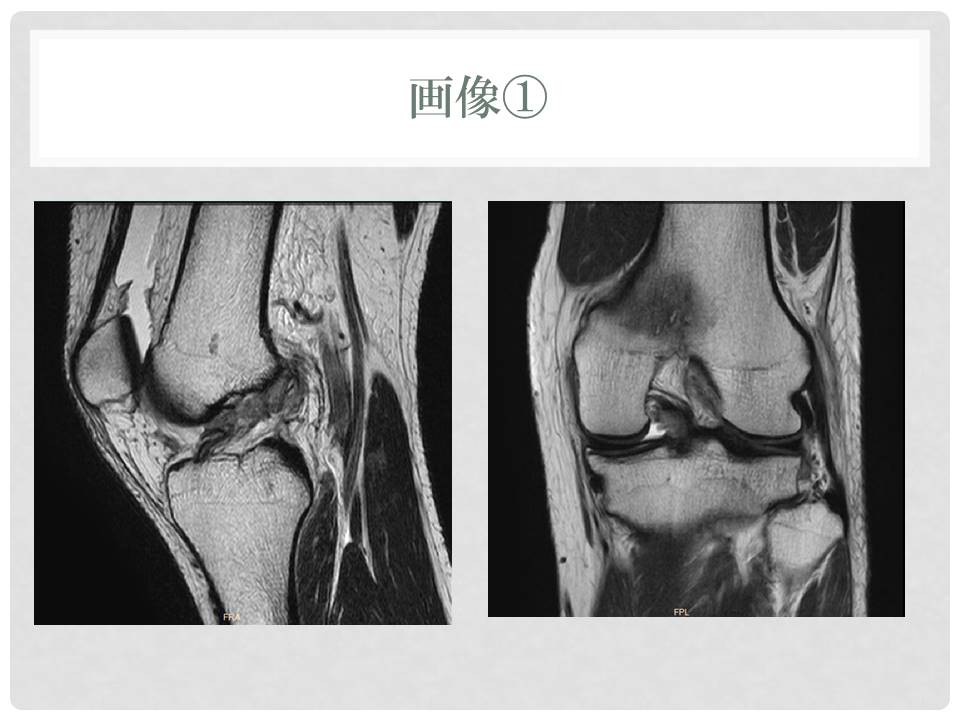

医療機関によるレントゲンなどの画像診断は済んでいます

スライド1